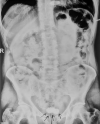

Figure 1

Preoperative kidney, ureter, and bladder showing entire coiled double J stent with a stone in the bladder in contact with it accompanied by encrustation.